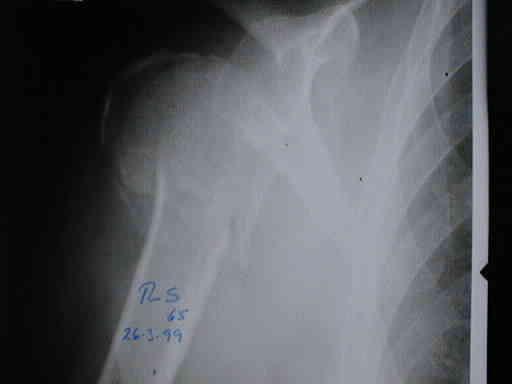

PRE - OPERATORIO

B1